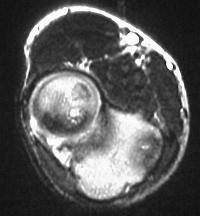

MRI shows an osteochondral sequestrum of the anterior capitellum: